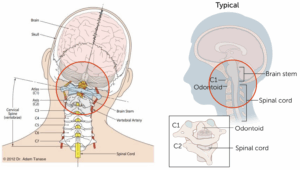

めまい、良性発作性頭位めまい症(BPPV)、平衡感覚の異常、眩暈がなかなか回復しない場合、その背景には頭蓋頸椎不安定性が隠れています。

頭蓋骨を支える第一頸椎であるAtlas(C1)と第二頸椎であるAxis(C2)から構成される上部頸椎のミスアライメントは、めまい、ブレインフォグ、離人症、認知機能および見当識障害(認知症症状)、メニエール病、良性発作性頭位めまい症、迷走神経性失神、自律神経機能障害、頭の中の圧迫感、頭がいっぱいになる頭痛、前頭部が重くなる頭痛、頭がぼんやりする状態、頭の中がもやもやして集中できない状態、後頸部と肩の痛みなど、様々な疾患において隠れた原因となっている場合が多くあります。